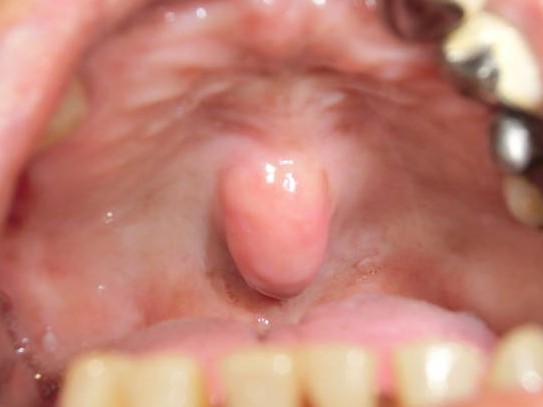

(1)口蓋隆起 torus palatinus